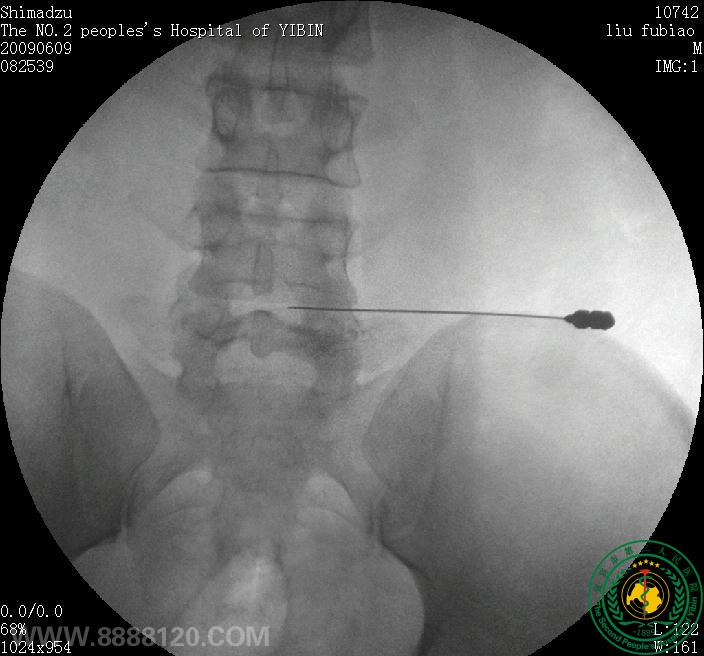

患者为30岁青年男性,经我院CT扫描诊断为腰4/5正中后型椎间盘突出症。经我科李登科、林川两位主治医师术前严格筛查及讨论,认为该患者适合进行臭氧髓核消融,无该手术禁忌症,遂于69日晨830分在经严格消毒后的介入手术室完成了该例手术。术中及术后患者未诉不适。术后于我院CT室复查,见腰4/5椎间盘髓核区臭氧存留。

术前CT                                                                      椎间盘穿刺(1

椎间盘穿刺(2                                                                         术后CT